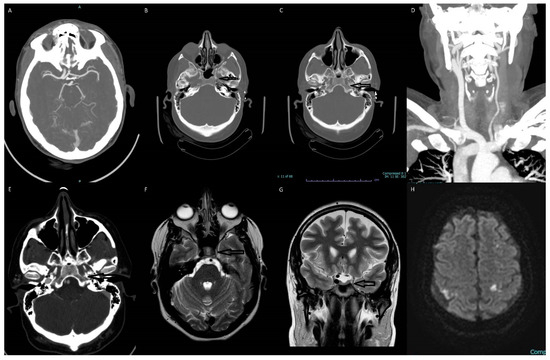

Figure 1. Multiple images depict the absence of the left internal carotid artery (ICA). (A) The transverse section of the CTA of the brain shows an absent supraclinoid segment of the ICA on the left side. The left anterior and middle cerebral arteries are reconstituted via the anterior communicating and posterior communicating arteries. (B) The axial section of the brain CT scan shows an absent horizontal petrous segment of ICA on the left side. (C) The axial section of the brain CT scan shows an absent vertical petrous segment of ICA on the left side. (D) Coronal MIP CTA showing arterial branching from the aortic arch and an absent left ICA. (E) The axial section of the CTA of the brain shows an absent vertical petrous segment of ICA on the left side. (F) The axial T2 weighted MR image shows absent flow void of left ICA. (G) The coronal T2 weighted MR image shows absent flow void of left ICA. (H) The brain MR diffusion-weighted imaging (DWI) showing focal regions of ischemia in bilateral cerebral hemispheres.

The most significant findings of the patient’s laboratory workup were an elevated troponin of 336 and a proBNP of 19,572. Her laboratory studies also demonstrated mild hypokalemia at 3.3, elevated BUN at 29, a creatinine of 1.47, a mildly elevated ALT of 53, and an INR of 1.18. Imaging studies included: Dx-Chest, Echocardiogram, MR-Brain-W/O, MRV Head, CT-CTA Neck with and W/O, CT-CTA head with and W/O. The patient’s echo showed severely reduced left ventricular systolic function with an ejection fraction of 30%, apical akinesis, and a thrombus present in the left ventricular apex. Brain magnetic resonance imaging showed tiny multifocal areas of acute infarcts in the bilateral frontal, parietal, and left occipital lobes in the watershed distribution. There was no visualization of the flow of the intracranial left internal carotid artery. The follow-up CTA of the head and neck showed a congenital absence of the left internal carotid artery with no evidence of arterial dissection, occlusion, or aneurysm.